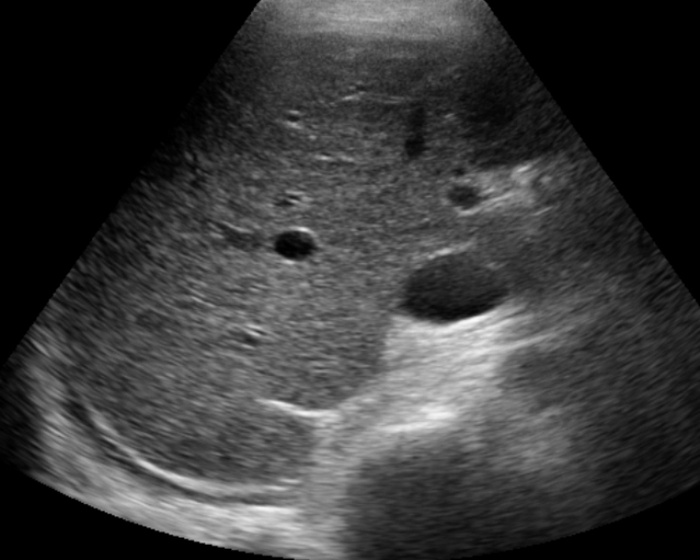

Polycystic Liver